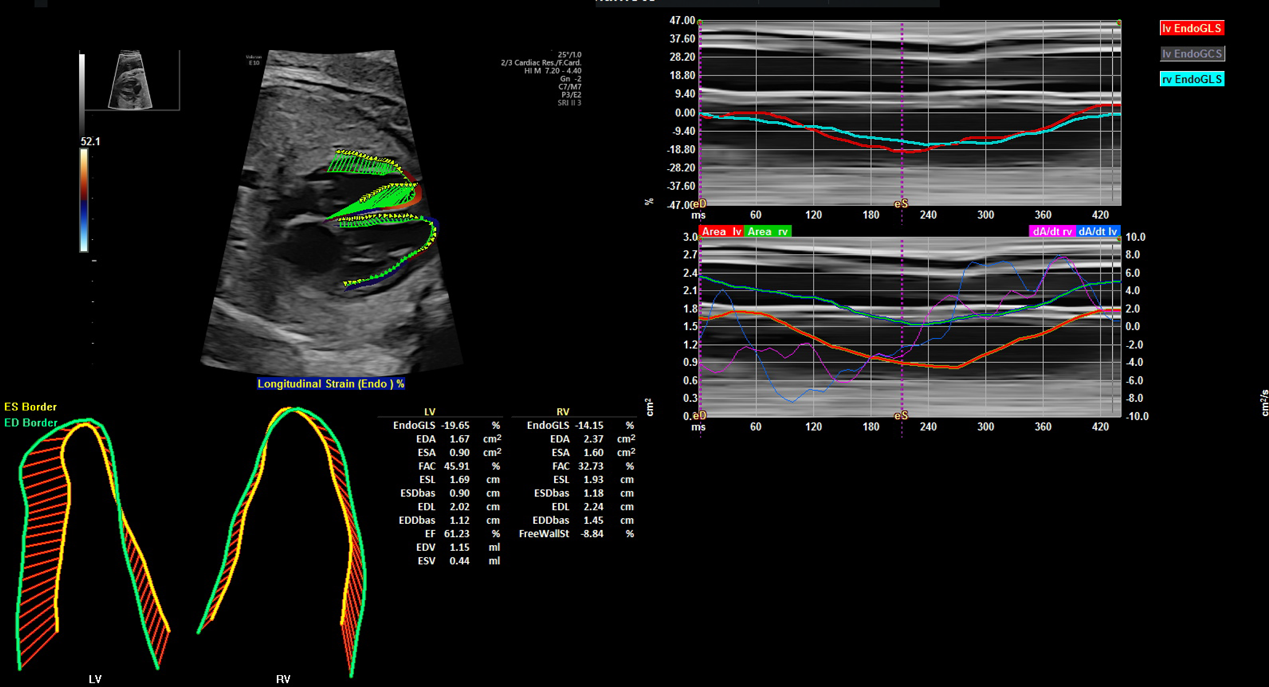

Speckle tracking(global longitudinal strain, strain rate):壁運動の定量化として成人や小児でも使用され,ストレインは心室の長軸方向の収縮機能指標で,特にGLS(global longitudinal strain)は心室全体の収縮性の指標である(Fig. 5).ストレインレート(global longitudinal strain rate: GLSR)はストレイン指標に時間の概念を加え,心筋の拡張能の指標となる.組織ドプラ法とは異なり,角度依存性がないため,明確な四腔断面の描出により計測が可能な点は優れている.胎児では心拍数が速いため,可能な限り高いframe rateでの撮像が望まれる.正常胎児におけるGLSやGLSRの変化を報告したものは散見されるが,さまざまな要因の影響を受けるために未だ一定の見解は得られていない.週数とともに低下としている研究15, 16)が多く,2022年に報告された124例の胎児の縦断研究では週数とともにGLSは低下し,右GLS=−24.57+0.2074×週数,左GLS=−26.73+0.2024×週数としている15)

Pediatric Cardiology and Cardiac Surgery 40(2): 103-112 (2024)

Fig. 5 Speckle tracking法